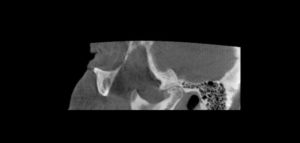

158 – Uso intraoperatorio de la CBCT para la identificación y localización de canales calcificados

Se sabe que la tomografía computarizada de haz cónico (CBCT) produce exploraciones tridimensionales de la dentición, las estructuras duras maxilofaciales y la relación de las